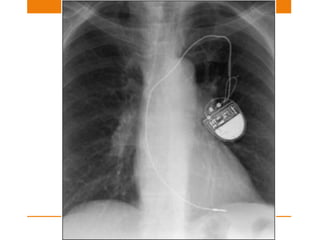

Pacemaker

SINGLE OR DUAL CHAMBER

Single chamber –nowadays used less frequently

• used for atrial or ventricular dysarrythmia

• Atrial – positioned in right atrial appendage

• Ventricular – Electrode placed against myocardium at

apex of right ventricle

Dual pacemaker

• Attempts to synchronize atrial and ventricular system

• One electrode @ Right atrium

• Other electrode @ apex of right ventricle

Sometimes a third lead is also noted

• Third –coronary sinus <Biventricular pacing>